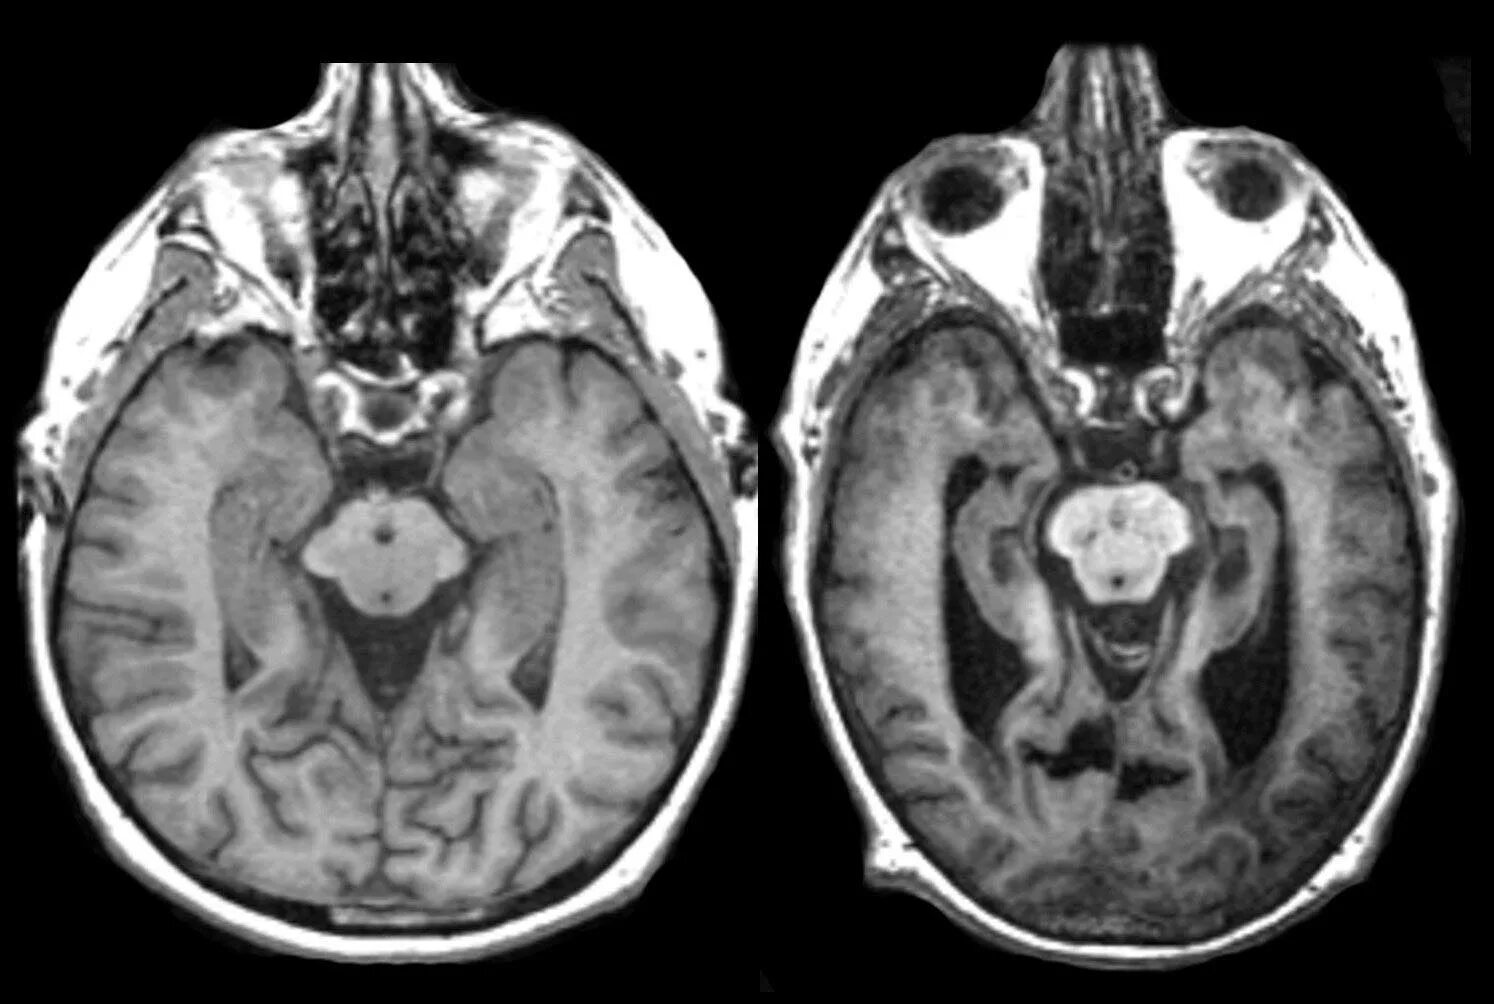

Мрт при каких заболеваниях